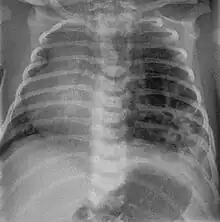

Three quarters of affected patients are asymptomatic. However, 25% develop cyanosis, pneumothorax, and show signs of increased breathing difficulty (tachypnoea and intercostal retractions).At examination, they may show hyper-resonance at percussion, diminished vesicular murmur and an asymmetrical thorax.

CPAMs are often identified during routine prenatal ultrasonography. Identifying characteristics on the sonogram include: an echogenic (bright) mass appearing in the chest of the fetus, displacement of the heart from its normal position, a flat or everted (pushed downward) diaphragm, or the absence of visible lung tissue.

CPAMs are classified into three different types based largely on their gross appearance. Type I has a large (>2 cm) multiloculated cysts. Type II has smaller uniform cysts. Type III is not grossly cystic, referred to as the "adenomatoid" type. Microscopically, the lesions are not true cysts, but communicate with the surrounding parenchyma. Some lesions have an abnormal connection to a blood vessel from an aorta and are referred to as "hybrid lesions."

Imaging

The earliest point at which a CPAM can be detected is by prenatal ultrasound. The classic description is of an echogenic lung mass that gradually disappears over subsequent ultrasounds. The disappearance is due to the malformation becoming filled with fluid over the course of the gestation, allowing the ultrasound waves to penetrate it more easily and rendering it invisible on sonographic imaging. When a CPAM is rapidly growing, either solid or with a dominant cyst, they have a higher incidence of developing venous outflow obstruction, cardiac failure and ultimately hydrops fetalis. If hydrops is not present, the fetus has a 95% chance of survival. When hydrops is present, risk of fetal demise is much greater without in utero surgery to correct the pathophysiology. The greatest period of growth is during the end of the second trimester, between 20–26 weeks.